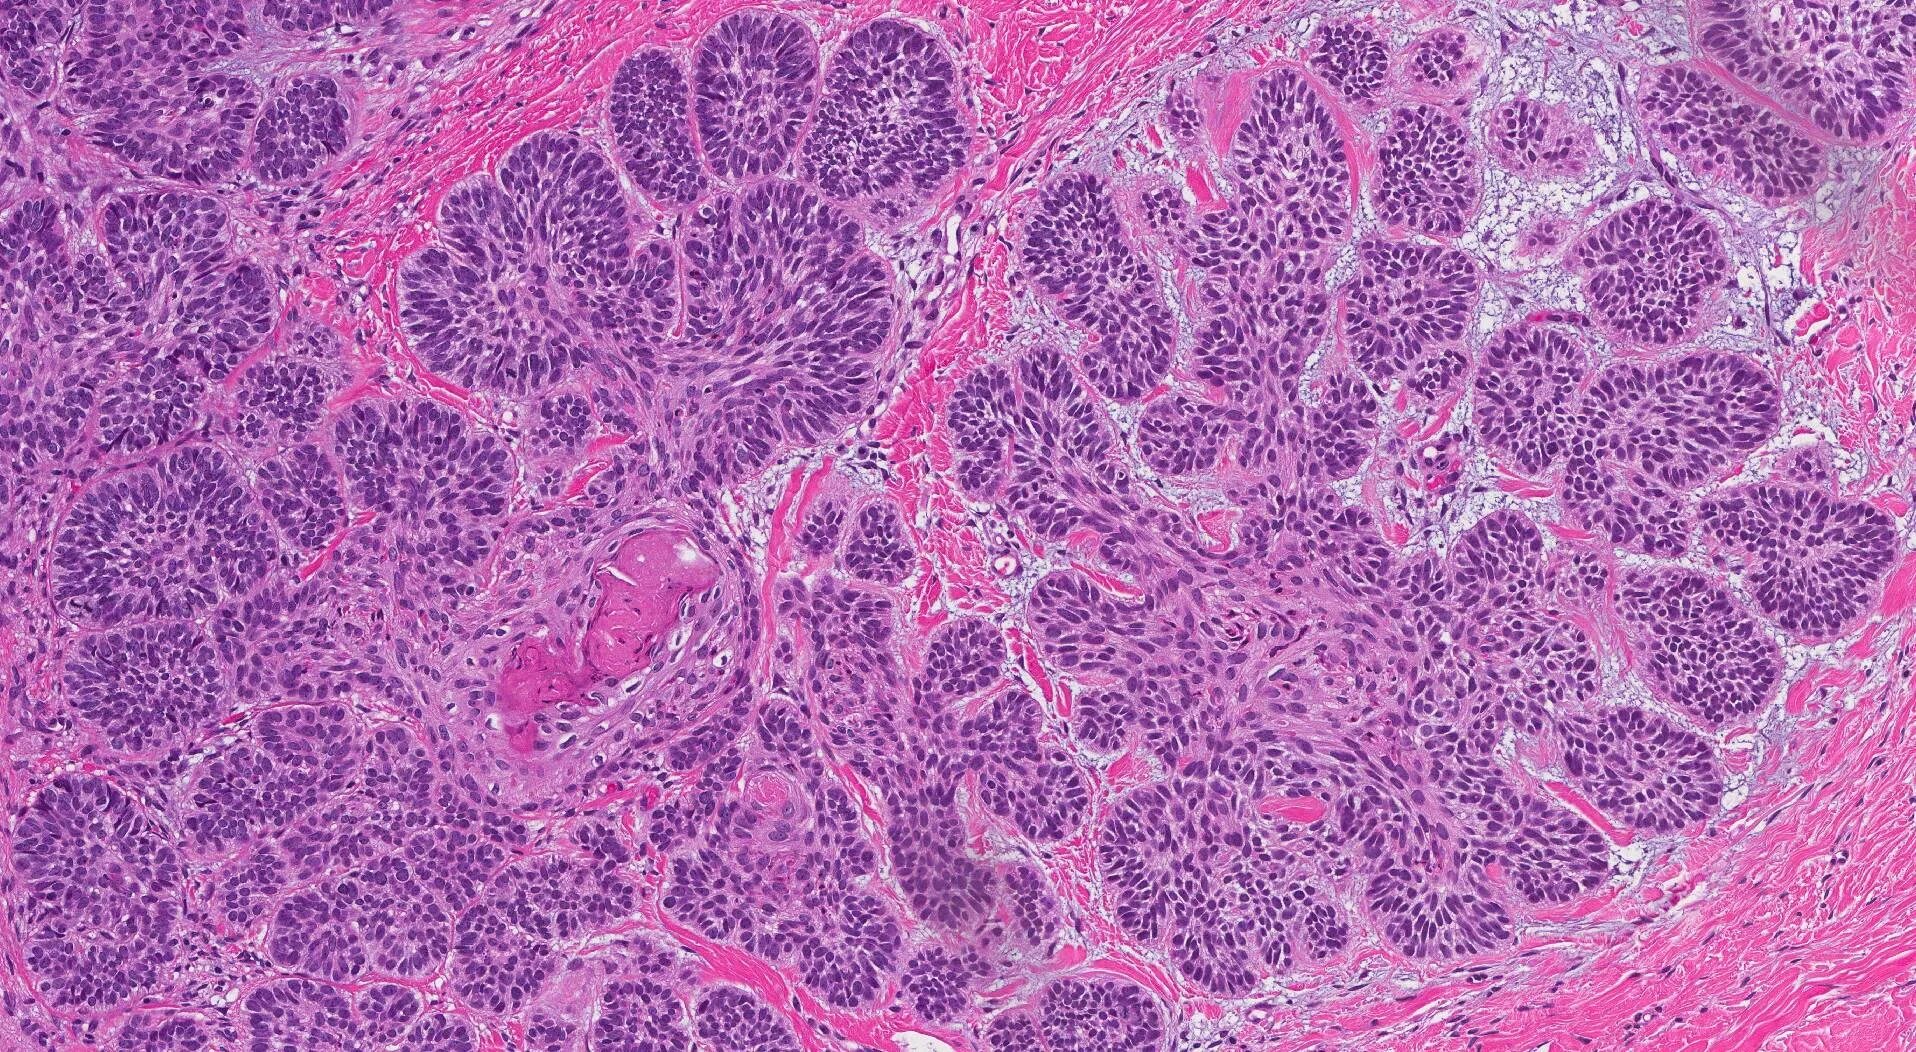

Базальная опухоль